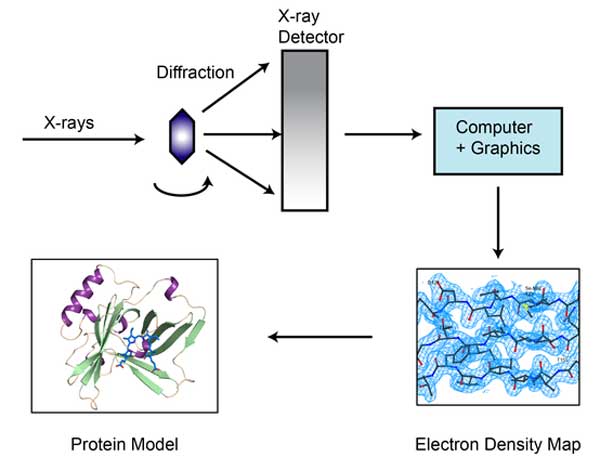

মহাকাশে পৃথিবীর মতো বাসযোগ্য ভিন গ্রহ খুঁজতে হাবল ও কেপলার স্পেস টেলিস্কোপের নিরিখে অনেক বেশি শক্তিশালী জেমস ওয়েব স্পেস টেলিস্কোপ (জেডব্লিউএসটি) পাঠানো হচ্ছে, ২০১৮-য়। ঠিক তেমনই জটিল রোগের নতুন নতুন ওষুধ আবিষ্কারের জন্য যেটা সবচেয়ে জরুরি, সেই আমাদের শরীরের সরল ও জটিল প্রোটিন অণুর গঠন-কাঠামো বা তাদের গঠন-সজ্জা (স্ট্রাকচার) আর দেহে তাদের চলাচলকে (ডায়নামিক্স) আরও ঝকঝকে ও নিখুঁত ভাবে দেখার জন্য বাজারে চালু দু’টি পদ্ধতি- ‘এক্স-রে ক্রিস্টালোগ্র্যাফি’ (এক্সআরসি) আর ‘নিউক্লিয়ার ম্যাগনেটিক রেজোন্যান্স’ (এনএমআর)-র চেয়ে অনেক অনেক গুণ বেশি শক্তিশালী এই ‘ক্রায়ো-ইএম’। যা জটিল থেকে জটিলতর প্রোটিনগুলির (কমপ্লেক্স প্রোটিন) পরমাণু স্তরের খবরাখবরও এখন দিতে পারছে। তার ফলে, জটিল প্রোটিনগুলির গঠন-কাঠামো আর আমাদের শরীরে তাদের চলাচলকে ওই অসম্ভব শক্তিশালী মাইক্রোস্কোপ ‘ক্রায়ো-ইএম’-এর মাধ্যমে চাক্ষুষ করাটা সম্ভব হচ্ছে। আগের চেয়ে অনেক অনেক বেশি সহজ হচ্ছে। স্পষ্ট থেকে স্পষ্টতর (হাই রেজোলিউশন) হচ্ছে। এত দিন এক্স-রে ক্রিস্টালোগ্র্যাফি আর নিউক্লিয়ার ম্যাগনেটিক রেজোন্যান্স পদ্ধতিতে যা করা যেত না। খুব কষ্টেসৃষ্টে তা যদি করা যেতও, তার ফলাফল নির্ভুল হত না।

এখন যে ভাবে কাজ চলে, সেই এক্স-রে ক্রিস্টালোগ্র্যাফি

এক্স-রে ক্রিস্টালোগ্র্যাফিতে যে ভাবে দেখা হয় প্রোটিন কেলাস

এক্স-রে ক্রিস্টালোগ্র্যাফিতে যে ভাবে দেখা হয় প্রোটিন কেলাস

এক, ‘ক্রায়ো-ইএম’ পদ্ধতিতে কাজটা করতে দ্রবণ বা সলিউশনের প্রয়োজন হয়। মানে, একটা তরল অবস্থা। যাতে একই সঙ্গে অনেকগুলি প্রোটিন থাকে। তবে তা স্বাভাবিক তাপমাত্রার তরল অবস্থা নয়। ‘ফ্রোজেন লিক্যুইড’ অবস্থা। মানে, হিমাঙ্ক বা ‘ফ্রিজিং পয়েন্ট’ বা শূন্য ডিগ্রি সেন্টিগ্রেডের নীচে থাকা অবস্থা। যা আদতে কঠিন। কিন্তু কেলাস বা ‘ক্রিস্টাল’ নয়। ফলে, একই সঙ্গে অনেকগুলি প্রোটিনের গঠন-কাঠামো আর তাদের চলাচলকে দেখা যায় ‘ক্রায়ো-ইএম’ পদ্ধতিতে। এটা এক্স-রে ক্রিস্টালোগ্র্যাফিতে সম্ভব নয়। কারণ, ওই পদ্ধতিতে প্রোটিন শুধুই কোনও কেলাস (ক্রিস্টাল, মানে, কঠিন পদার্থ) অবস্থায় থাকলে, তবেই তাকে দেখা যায়। আর যেহেতু ওই পদ্ধতিতে কোনও দ্রবণ থাকে না, তাই একই সঙ্গে একাধিক প্রোটিন অণুর গঠন-কাঠামো দেখার সুযোগ থাকে না এক্স-রে ক্রিস্টালোগ্র্যাফিতে।

তিন, দশায় দশায় কোনও প্রোটিন অণু বা অণুগুলির ‘রূপবদল’ হয়। এটাকে বলে ‘ফেজ ট্রান্সফর্মেশন’। তাদের অবস্থার পরিবর্তন। সেই পরিবর্তনের কিছু গুরুত্বপূর্ণ সংকেত থাকে, বার্তা থাকে। যাদের বলা হয় ‘ফেজ ইনফর্মেশন’। এই ‘ফেজ ইনফর্মেশন’-এর অনেকটাই এক্স-রে ক্রিস্টালোগ্র্যাফিতে হারিয়ে যায়। যা ‘ক্রায়ো-ইএম’-এ কোনও দিনই হবে না।

চার, সে জন্যই ‘ক্রায়ো-ইএম’ পদ্ধতির ছবির রেজোলিউশন অত ভাল, অত নিখুঁত, অত সূক্ষ্ণ হয়।